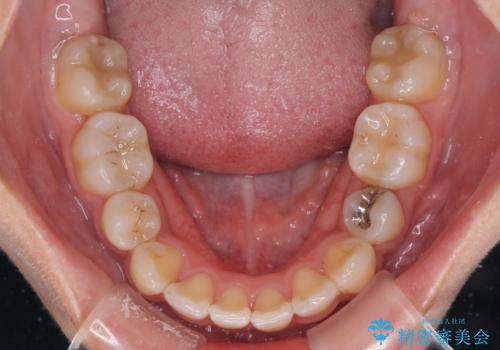

- 上下前歯のデコボコと、それによる磨きづらさを気にして来院された患者様です。

叢生解消のため、上下左右第一小臼歯4本を抜歯し、ワイヤー装置にて矯正治療を行うこととしました。